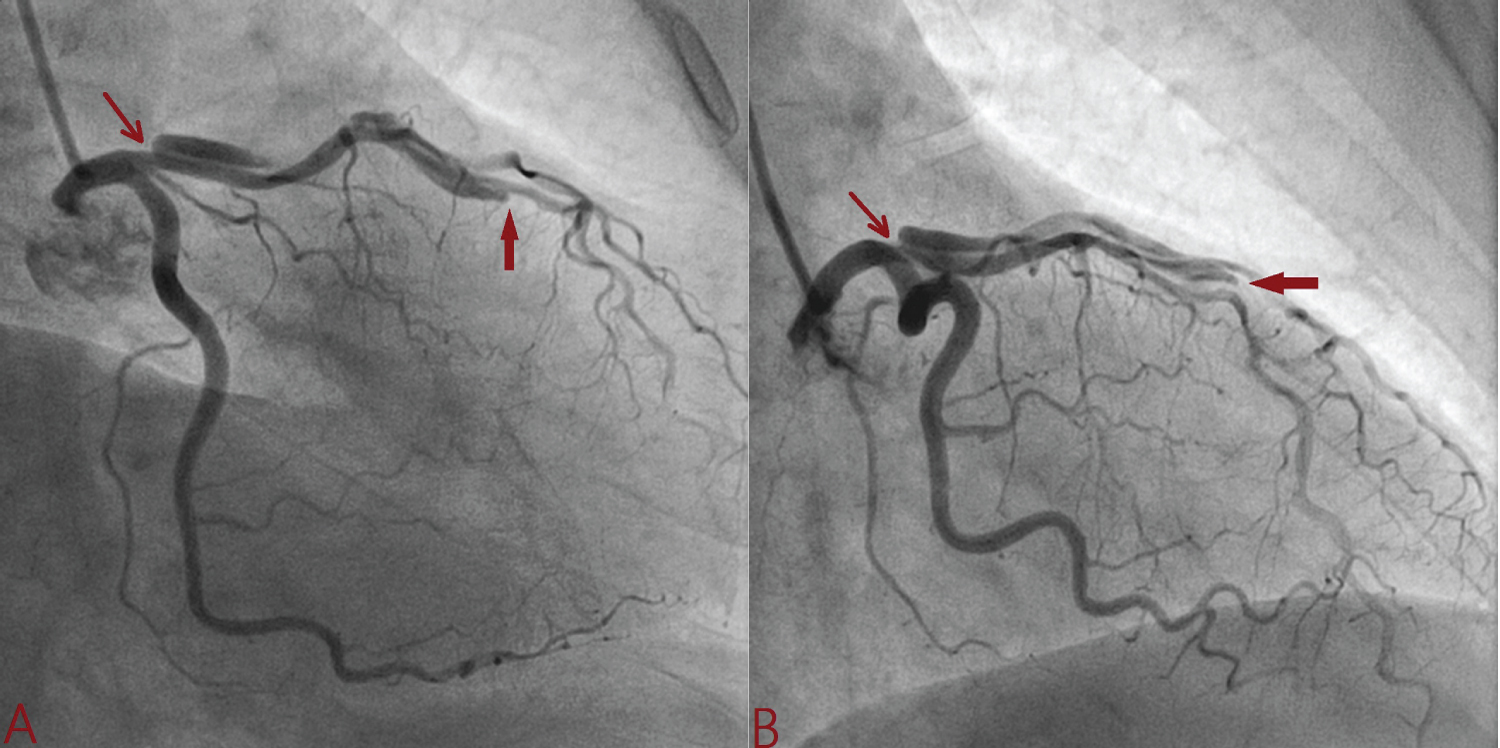

A 32-year-old apparently healthy male presented with excruciating chest pain with diaphoresis of 2-hour duration. His pulse rate was 85 beats/min and blood pressure was 110/84 mmHg. Other physical findings were all normal. Electrocardiogram showed normal sinus rhythm and ST-elevation in V1-V6 with reciprocal changes in inferior leads. An echocardiogram revealed regional wall motion abnormality in left anterior descending artery territory (LAD) with mild left ventricular (LV) systolic dysfunction (ejection fraction = 45%). His routine blood examinations were normal. He was loaded with aspirin 300 mg, clopidogrel 300 mg and thrombolysed with 40 mg Tenecteplase. At 90 minute, chest pain was persistent with little resolution of ST segment (≤ 50% from initial elevation) which indicated failed lyses. Coronary angiography was performed through transfemoral after obtaining written consent. LAD showed large, spontaneous spiral dissection with flap beginning from osteo-proximal segment extending up to mid segment involving first diagonal branch which was labelled as Type-D SCAD (Figure 1 and Figure 2). As the origin of dissection flap was appreciated on first injection and originating away from the ostial segment of LAD, it ruled out iatrogenic dissection. The rest of his coronary trees were normal. PCI was advised PCI but patient refused. He was conservatively managed with Ecospirin 75 mg, Clopidogrel 75 mg, Rosuvastatin 10 mg, Ramipril 5 mg and Metoprolol 100 mg. Repeat angiogram 4-weeks later revealed complete healing of dissection along with borderline lesion (Figure 3). Echocardiography indicated normalization of systolic function (ejection fraction-70%). As his treadmill test was negative for exercise induced myocardial ischaemia, he was managed conservatively.

Figure 1: Spiral dissection extending from osteo-proximal left anterior descending artery involving its large diagonal branch (A: Antero-posterior caudal view; B: Right anterior oblique caudal view. Red arrow indicate intimal flap). View Figure 1